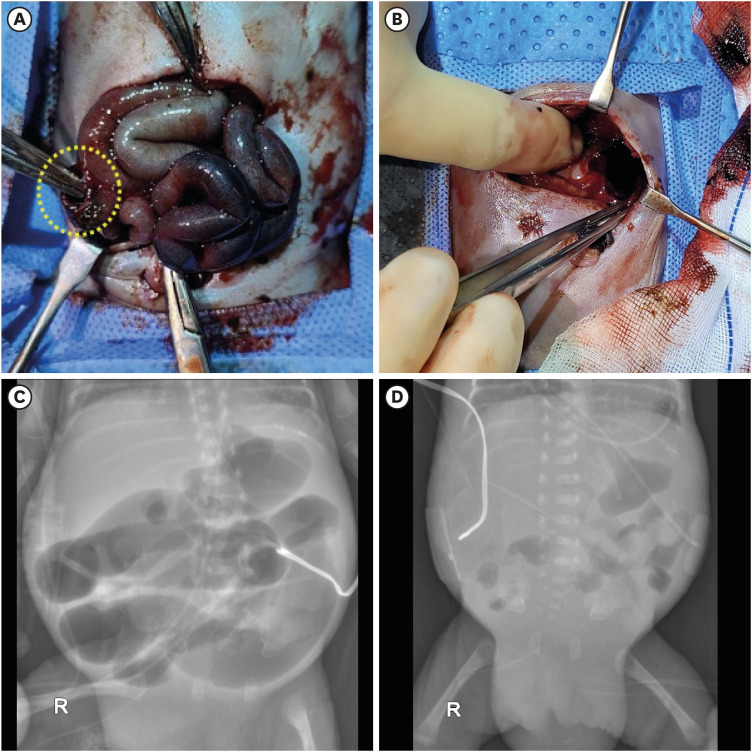

我们报告的情况下,两个极早产儿谁是成功地治疗组织纤溶酶原激活剂(tPA)对危及生命的阻塞性腔内血肿。一名婴儿因胃肠道血肿出现肠穿孔和肠梗阻,而另一名婴儿因气管内血肿出现肺萎陷。分别将tPA直接应用于胃肠道和气管,导致血肿溶解和阻塞缓解。对于治疗方案有限的极早产儿,局部tPA可能是治疗导致胃肠道梗阻或肺萎陷的严重阻塞性腔内血肿的一种有价值的方法。

We report the cases of two extremely preterm infants who were successfully treated with tissue plasminogen activator (tPA) for a life-threatening obstructive intraluminal hematoma. One infant presented with bowel perforation and ileus resulting from a gastrointestinal (GI) hematoma, whereas the other experienced lung collapse due to an intratracheal hematoma. Direct administration of tPA to the GI tract and trachea, respectively, resulted in hematoma lysis and relief of the obstruction. For extremely preterm infants with limited viable treatment options, local tPA may be a valuable approach for managing severe obstructive intraluminal hematomas that lead to GI obstruction or lung collapse.